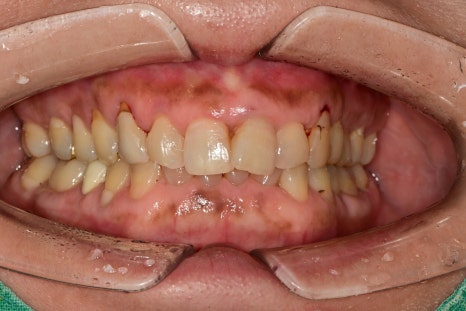

치열이 고르지 않은 위 앞니를 가지런하게 하고 싶다는 주소였습니다.

양쪽 송곳니는 오래된 보철, 수복물에 의해 재치료가 필요해 보였습니다.

나머지 4개의 앞니에서는 가운데 치아만 살짝 겹쳐 있어 보이는 것으로 보이지만

위에서 바라보는 사진은 완전히 달랐습니다.